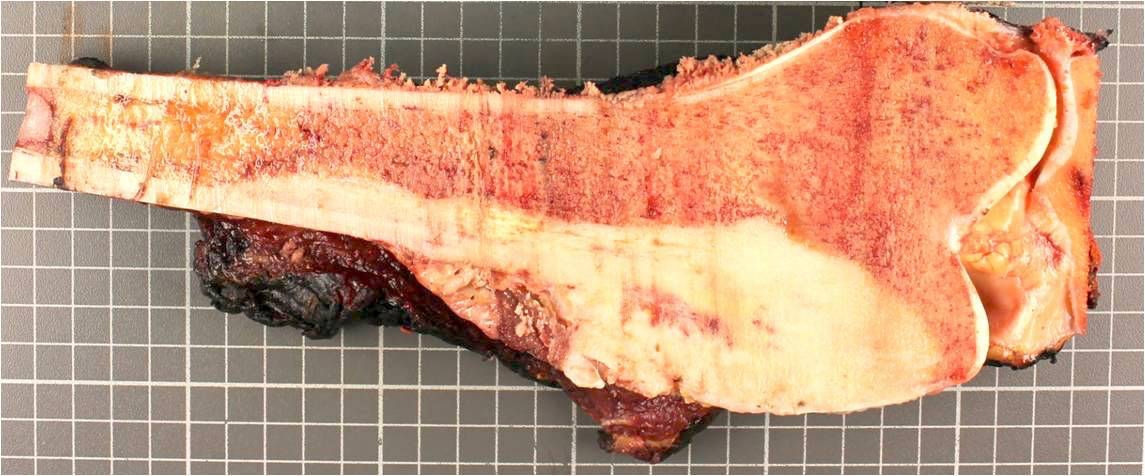

- Assessment of preoperative chemotherapy:

- Preoperative chemotherapy is commonly used with limb salvage procedures for treatment of high grade sarcomas, particularly osteosarcoma and Ewing sarcoma

- It is generally required to quantify the extent of tumor necrosis as a percentage of the total tumor area

- For osteosarcomas, chemotherapy induced necrosis of ≥ 90% has a > 90% disease free survival, compared with < 50% in patients with < 90% tumor necrosis

- To determine the extent of necrosis in an osteosarcoma or Ewing sarcoma specimen, the slab specimen of the resected bone containing tumor provides the template for histologic analysis

- Photograph of the slice is taken and the site of each numbered block is marked on a grid pattern diagram

- Status postneoadjuvant chemotherapy:

- To gross: cut along long axis of tumor and map

- References: Cancer 1982;49:1679, Onco Targets Ther 2013;6:593

Gross images